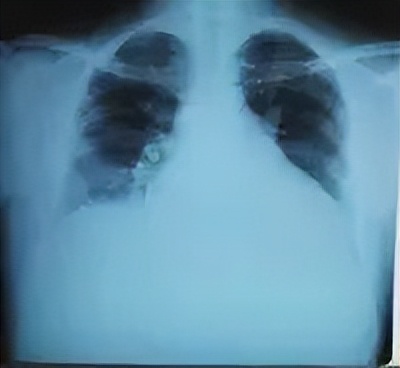

X线检查

心脏扩大为突出表现,以 左心室扩大 为主,伴以右心室扩大,也可有左心房及右心房扩大。心衰时扩大明显,心衰控制后,心脏扩大减轻,心衰再次加重时,心脏再次扩大。呈“ 手风琴效应 ”。心脏搏动幅度普遍减弱,病变早期可出现节段性运动异常。主动脉正常,肺动脉轻度扩张,肺淤血较轻。